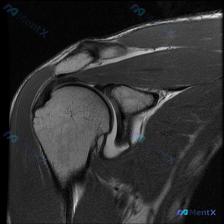

整理了一份肩部影像病例资料,核心情况如下: 1. 影像资料:肩部MRI T1加权冠状位序列 2. 核心疑问:临床怀疑盂唇病变,该序列影像下能观察到什么? 3. 初步影像所见:当前序列显示肱骨头、肩峰、冈上肌腱等结构大致完整,上方盂唇形态及信号未见明显异常,未见明确肩袖撕裂、骨性撞击征象。 想和大家讨...

最近看到一份单一T1加权冠状位肩关节MRI影像,想评估是否存在盂唇病变。但了解到MRI诊断肩关节病变往往需要多序列联合判断,仅凭T1序列有一定局限性。大家怎么看这个影像的诊断价值?

最近看到一个肩部MRI病例,资料里只有T1序列冠状位影像。影像分析显示:肱骨头、肩胛盂形态正常,冈上肌腱走行连续无撕裂,上方盂唇呈三角形低信号、轮廓规则,未见明显的信号异常或撕裂征象。 虽然影像没找到盂唇的结构性病变,但患者很可能有持续性肩痛症状(不然也不会做MRI)。大家第一眼看到这种情况,会先往...